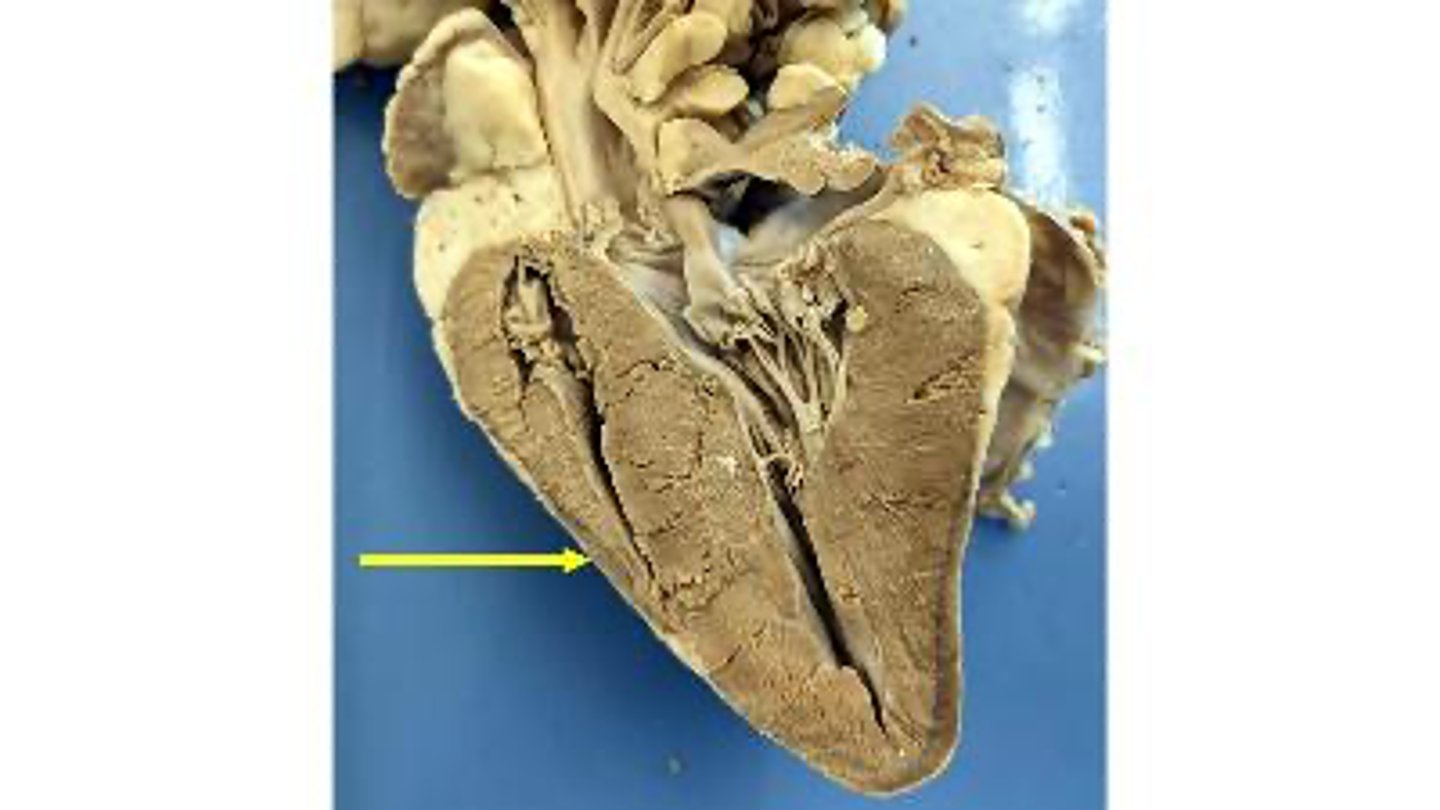

aortic valve

Name the membranous structure

right auricle

Name the ear-like structure

apex

Name the region of the organ

left ventricle

Name the chamber

interventricular septum

Name the dividing wall indicated

chordae tendineae

Name the structures

right ventricle